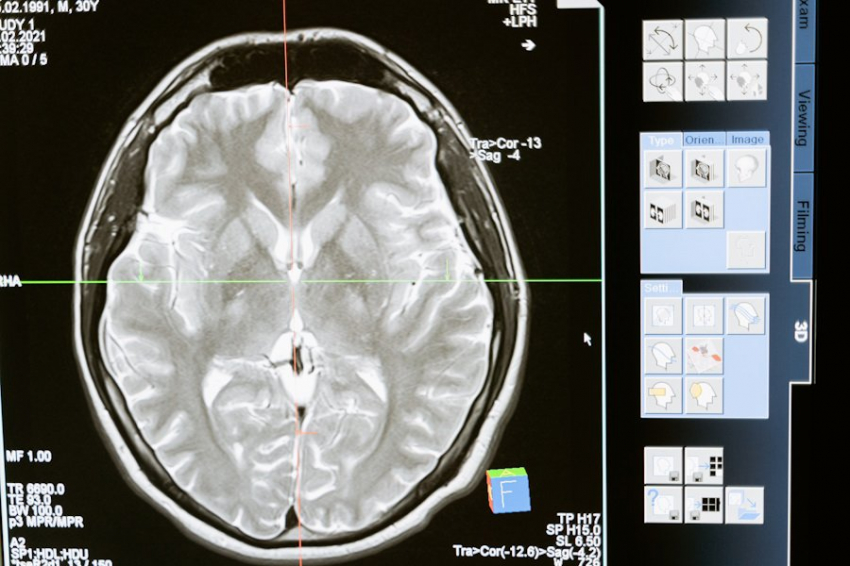

Впереди планеты всей — технологии и наука

Израиль — признанный мировой лидер в медицинской науке. Страна занимает 1-е место в мире по количеству научных открытий в медицине. Здесь не просто лечат — здесь создают стандарты, по которым затем начинают работать другие страны. Это лаборатория передовой медицины в прямом смысле слова.

Врачи в Израиле начинают применять новые технологии, препараты и терапевтические схемы на 4–6 лет раньше, чем это становится общепринятым в мировой практике. Диагностика здесь быстрее, точнее, а подход к терапии — мягче, безопаснее и эффективнее.